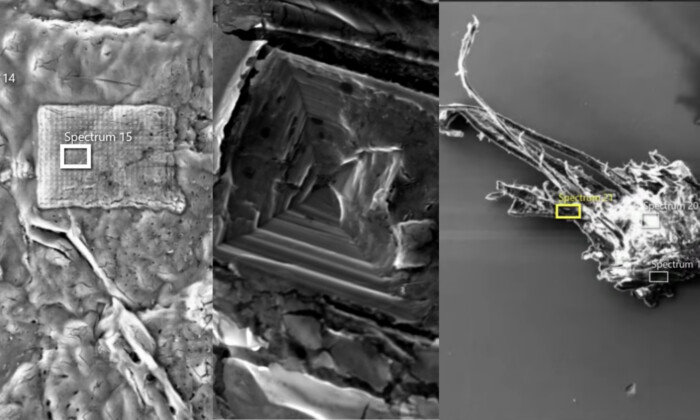

プラスチックに含まれる化学物質、心臓病による死亡と関連

1日前

プラスチックに含まれる化学物質、心臓病による死亡と関連

1日前